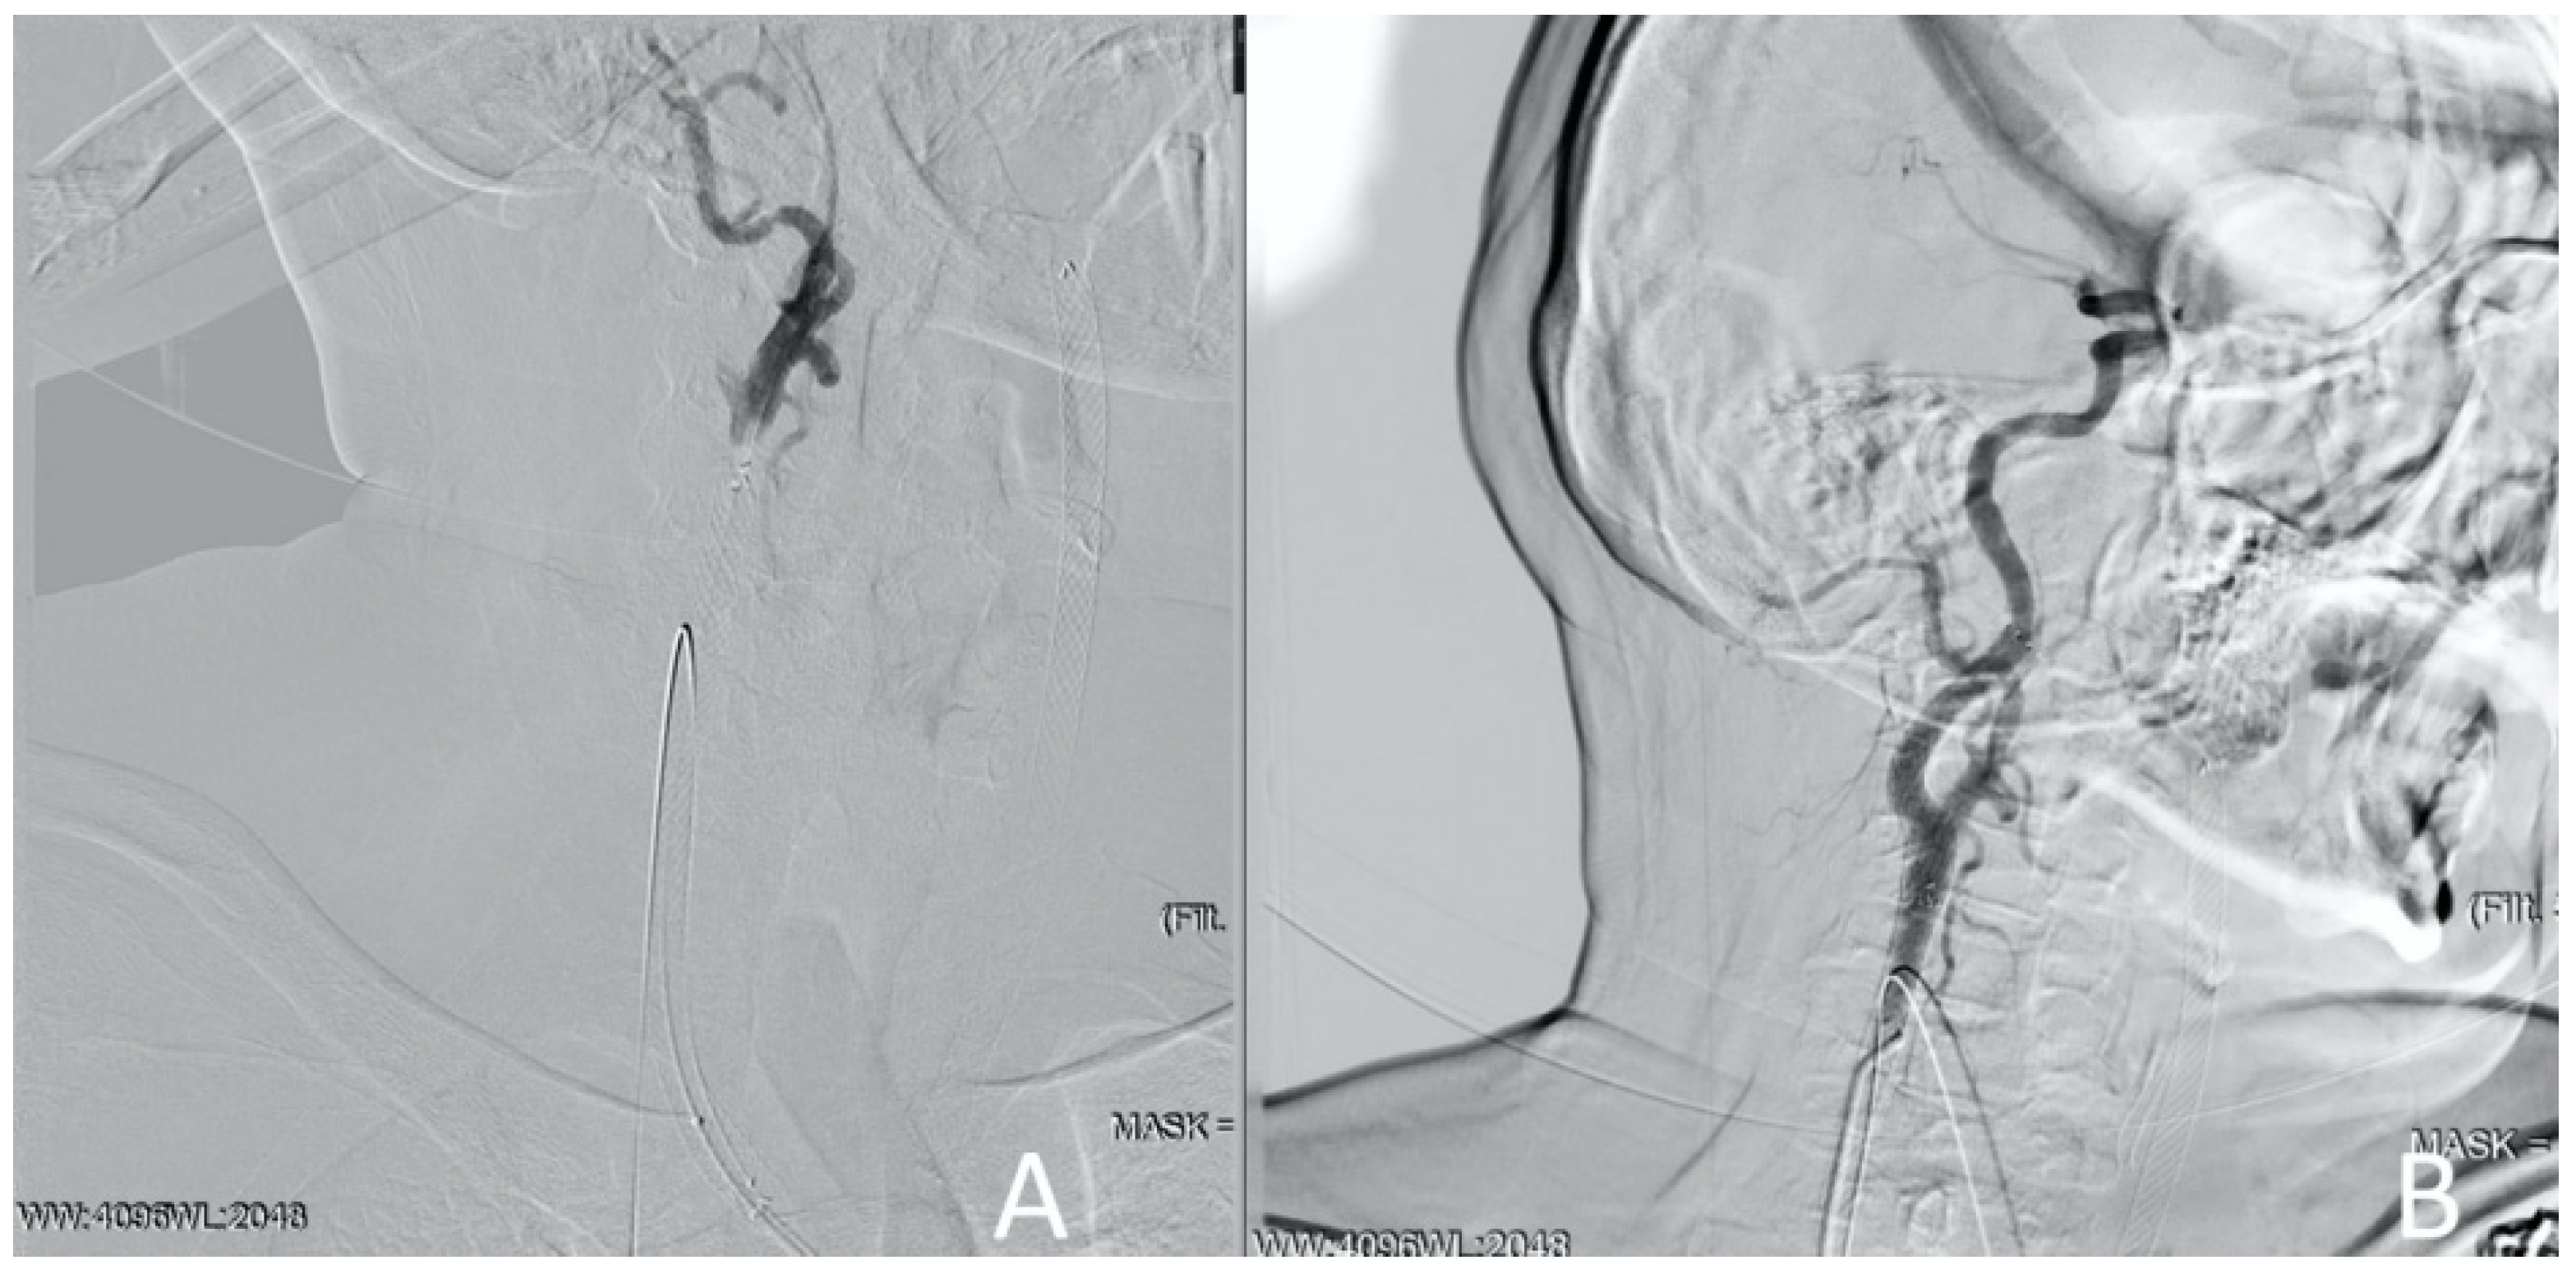

Considering the surgeon’s experience working with such patients (Clinical Case 1) as well as endovascular team engagement, it was decided to perform emergency endovascular cerebral reperfusion. The patient, without technical difficulties, got a self-expanding stent measuring 6.0 × 150 mm in the left internal and common carotid arteries with protrusion into the aorta; however, control angiography revealed the thrombotic occlusion of the ICA in segment C7. The thromboaspiration using a catheter (6Fr) was performed. Blood flow was restored at the level of TI-CI 2b-3 (Figure 11).

Figure 11.

Clinical Case 2, Patient S., male, 60 years old. Results of the angiography: (A) left ICA occlusion from the bifurcation, the external carotid artery is passable; (B) left ICA stenting with the stent protrusion into the aorta; (C) stagnation of contrast in ICA due to a thrombus in the C1 segment of the ICA; (D) restoration of blood flow through the cerebral arteries.

The left hemisphere circulation was restored in 90 min from the onset of the symptoms. The antegrade cannulation of the right CCA was technically impossible due to true lumen compression. Within 5 min, a retrograde puncture of the right CCA under ultrasound control was performed (Figure 12).

Figure 12.

Clinical Case 2, Patient S., male, 60 years old. Retrograde puncture of the right ICA.

The guide catheter was introduced into the descending aorta, and then into the left iliac artery, where it was externalized. It was decided not to remove the retrograde guide catheter from the CCA before installing the stent, since the compression during hemostasis could complicate the procedure. On the second guide catheter from the ICA orifice with protrusion into the aorta, a self-opening stent of 6.0 × 120 mm was implanted.

However, control angiography showed the absence of blood flow through the ICA due to the spread of hematoma to the C1 segment of the ICA. A cone stent of 8.0/10.0 × 40 mm was positioned in the ICA, with previously implanted stent overlap. The blood flow was totally restored. Right hemisphere revascularization was performed at 140 min from the onset of symptoms. Control angiography showed a complete restoration of cerebral circulation to the level of TICI-III (Figure 13).

Figure 13.

Clinical Case 2, Patient S., male, 60 years old. Right CCA revascularization. (A) Implantation of a 6.0 × 120 mm stent in CCA. No blood flow in ICA due to hematoma transition to the C1 segment. (B) Cone stent 8.0/10.0 × 40 mm implantation. Right hemisphere blood flow to TICI 3 level was totally restored.